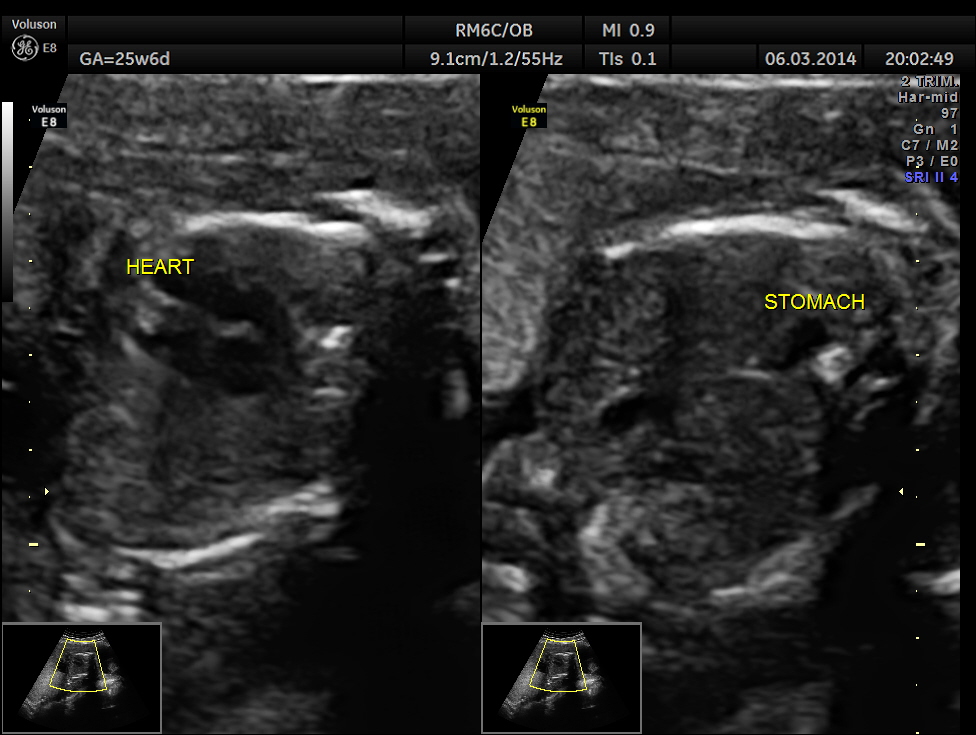

The GA was around 25 weeks , but the AUA was around 19 to 20 weeks. All parameters – BPD, HC, AC, FL are < 2.3 %tile and all other long bones are < 5.0 %tile.

Prominent placentomegaly seen .

Oligohydramnios seen.

Fetal kidneys are hyperechoic and enlarged.